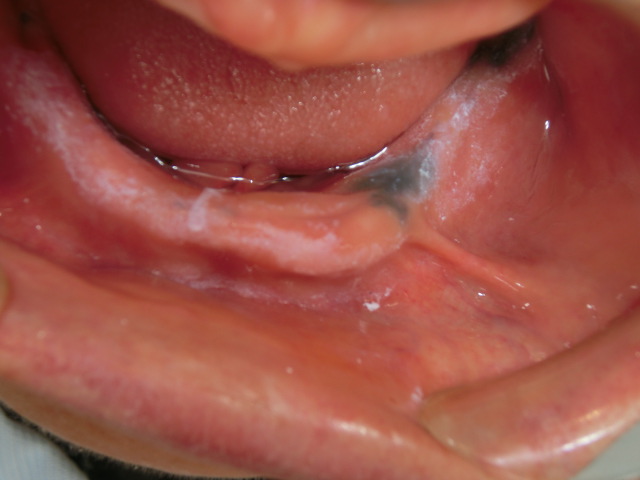

症例

症例3:組織検査では良性の診断。長期の経過を見ています。